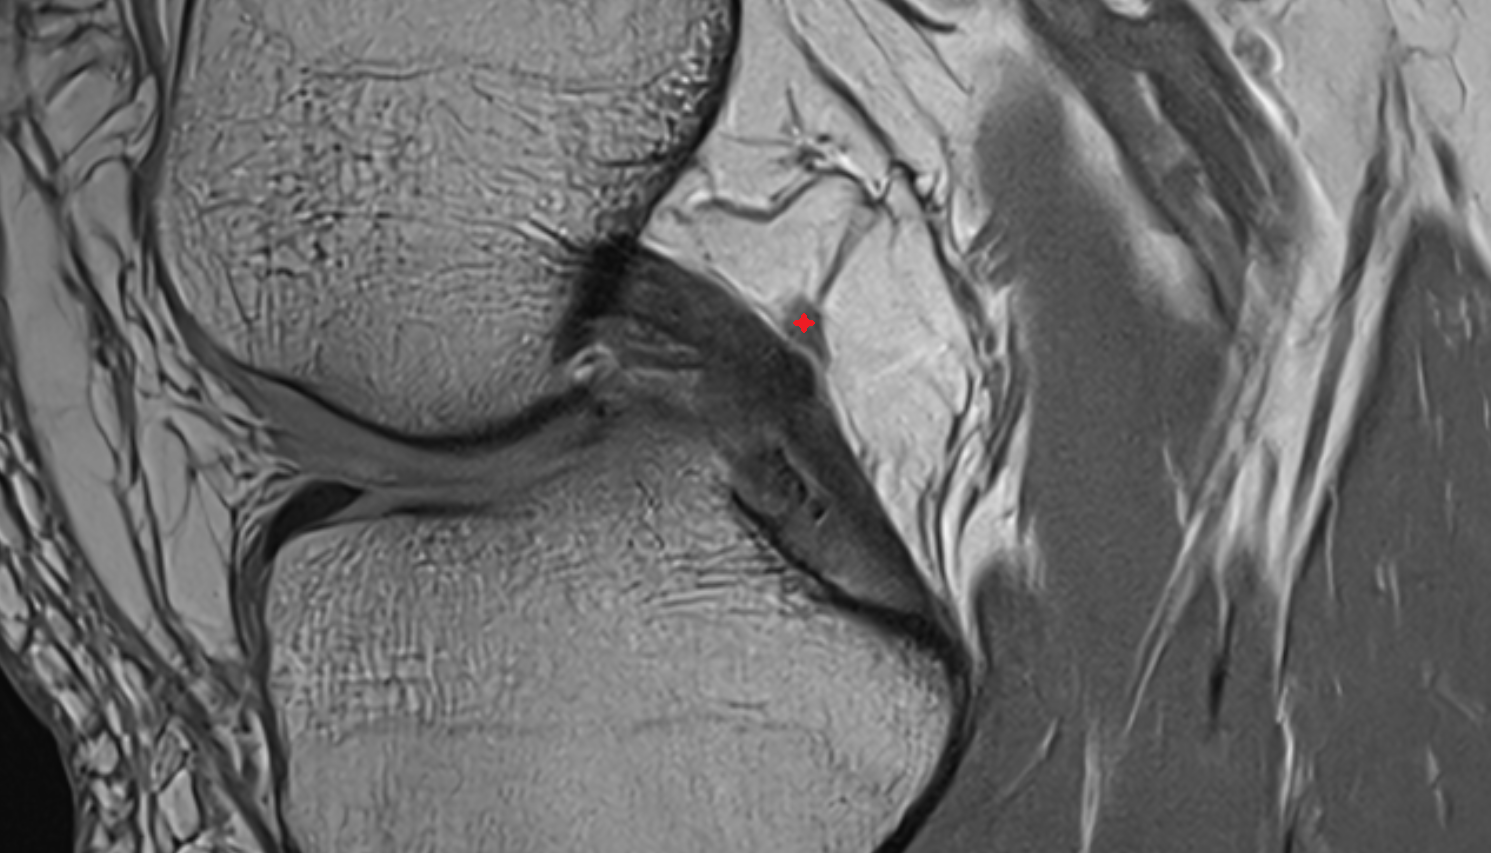

- Anterior cruciate ligament

- Posterior cruciate ligament